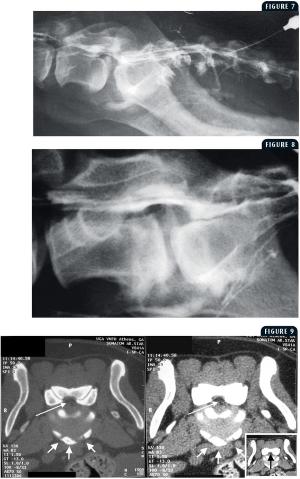

Degenerative lumbosacral stenosis is a common cause of cauda equina syndrome and a relatively frequent neurologic disorder in older dogs. If this condition is recognized early, treatment may help alleviate significant morbidity.